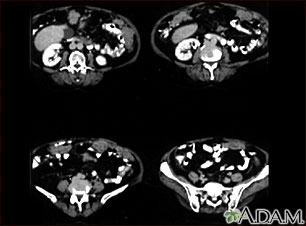

An abdominal CT scan is an imaging test that uses x-rays to create cross-sectional pictures of the belly area. CT stands for computed tomography.

A computer creates separate images of the belly area. These are called slices. These images can be stored, viewed on a monitor, printed on film or saved to a disk. Three-dimensional models of the belly area can be made by stacking the slices together.

In many cases, an abdominal CT is done with a pelvis CT.